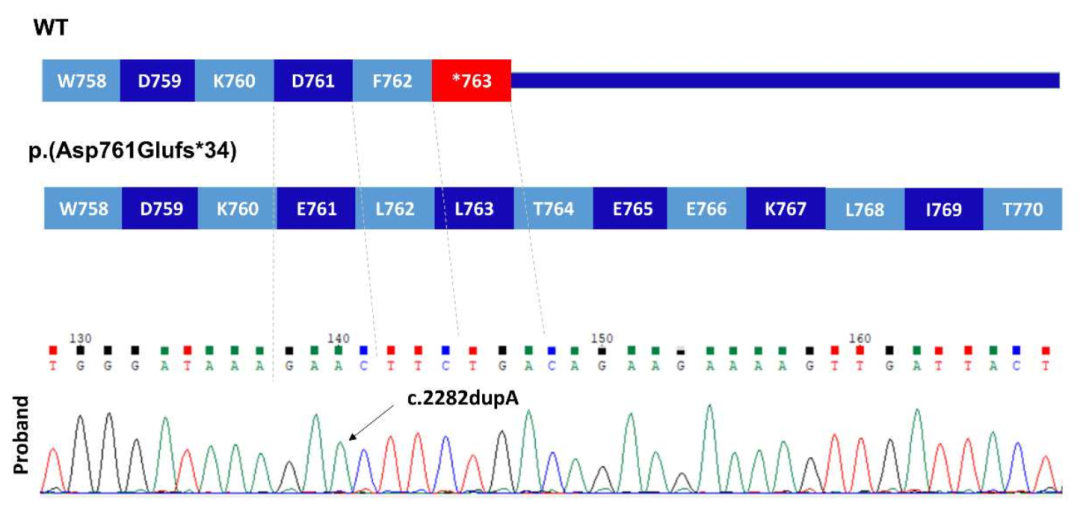

在家族1中,通过WGS和Sanger测序在3个患有椎体-骺端发育不良 (Spondylometaphyseal dysplasia, SMD)的兄弟中发现了一个纯合子致病突变PRKG2 (NM_006259.3:c.2282dup, p.Asp761Glufs*34)。有趣的是,F1-IV-6患者 (中度致病)也有I型成骨不全 (Type I osteogenesis imperfect, OI)。一项早期临床外显子组测序研究发现,在分子诊断的病例中,有4.6%的病例有一个以上的基因变异导致混杂 (Blended)表型。

家系1一代测序验证

插入A碱基后发生移码,且无法终止翻译

这里描述的这两种变异都非常罕见,gnomAD数据库中没有p.Asp761Glufs*34,而p.Arg569*为单基因。在这两个家系中,致病变异都存在于较大的ROHs中。虽然p.Arg569*突变已经被证明影响下游的MAPK途径,但家系1中的p.Asp761Glufs*34很可能也是有害的,因为蛋白C末端Asp>Phe及33个氨基酸发生替换。在计算机建模中的研究突出了该区域的结构重要性,特别是终末Phe762残基。